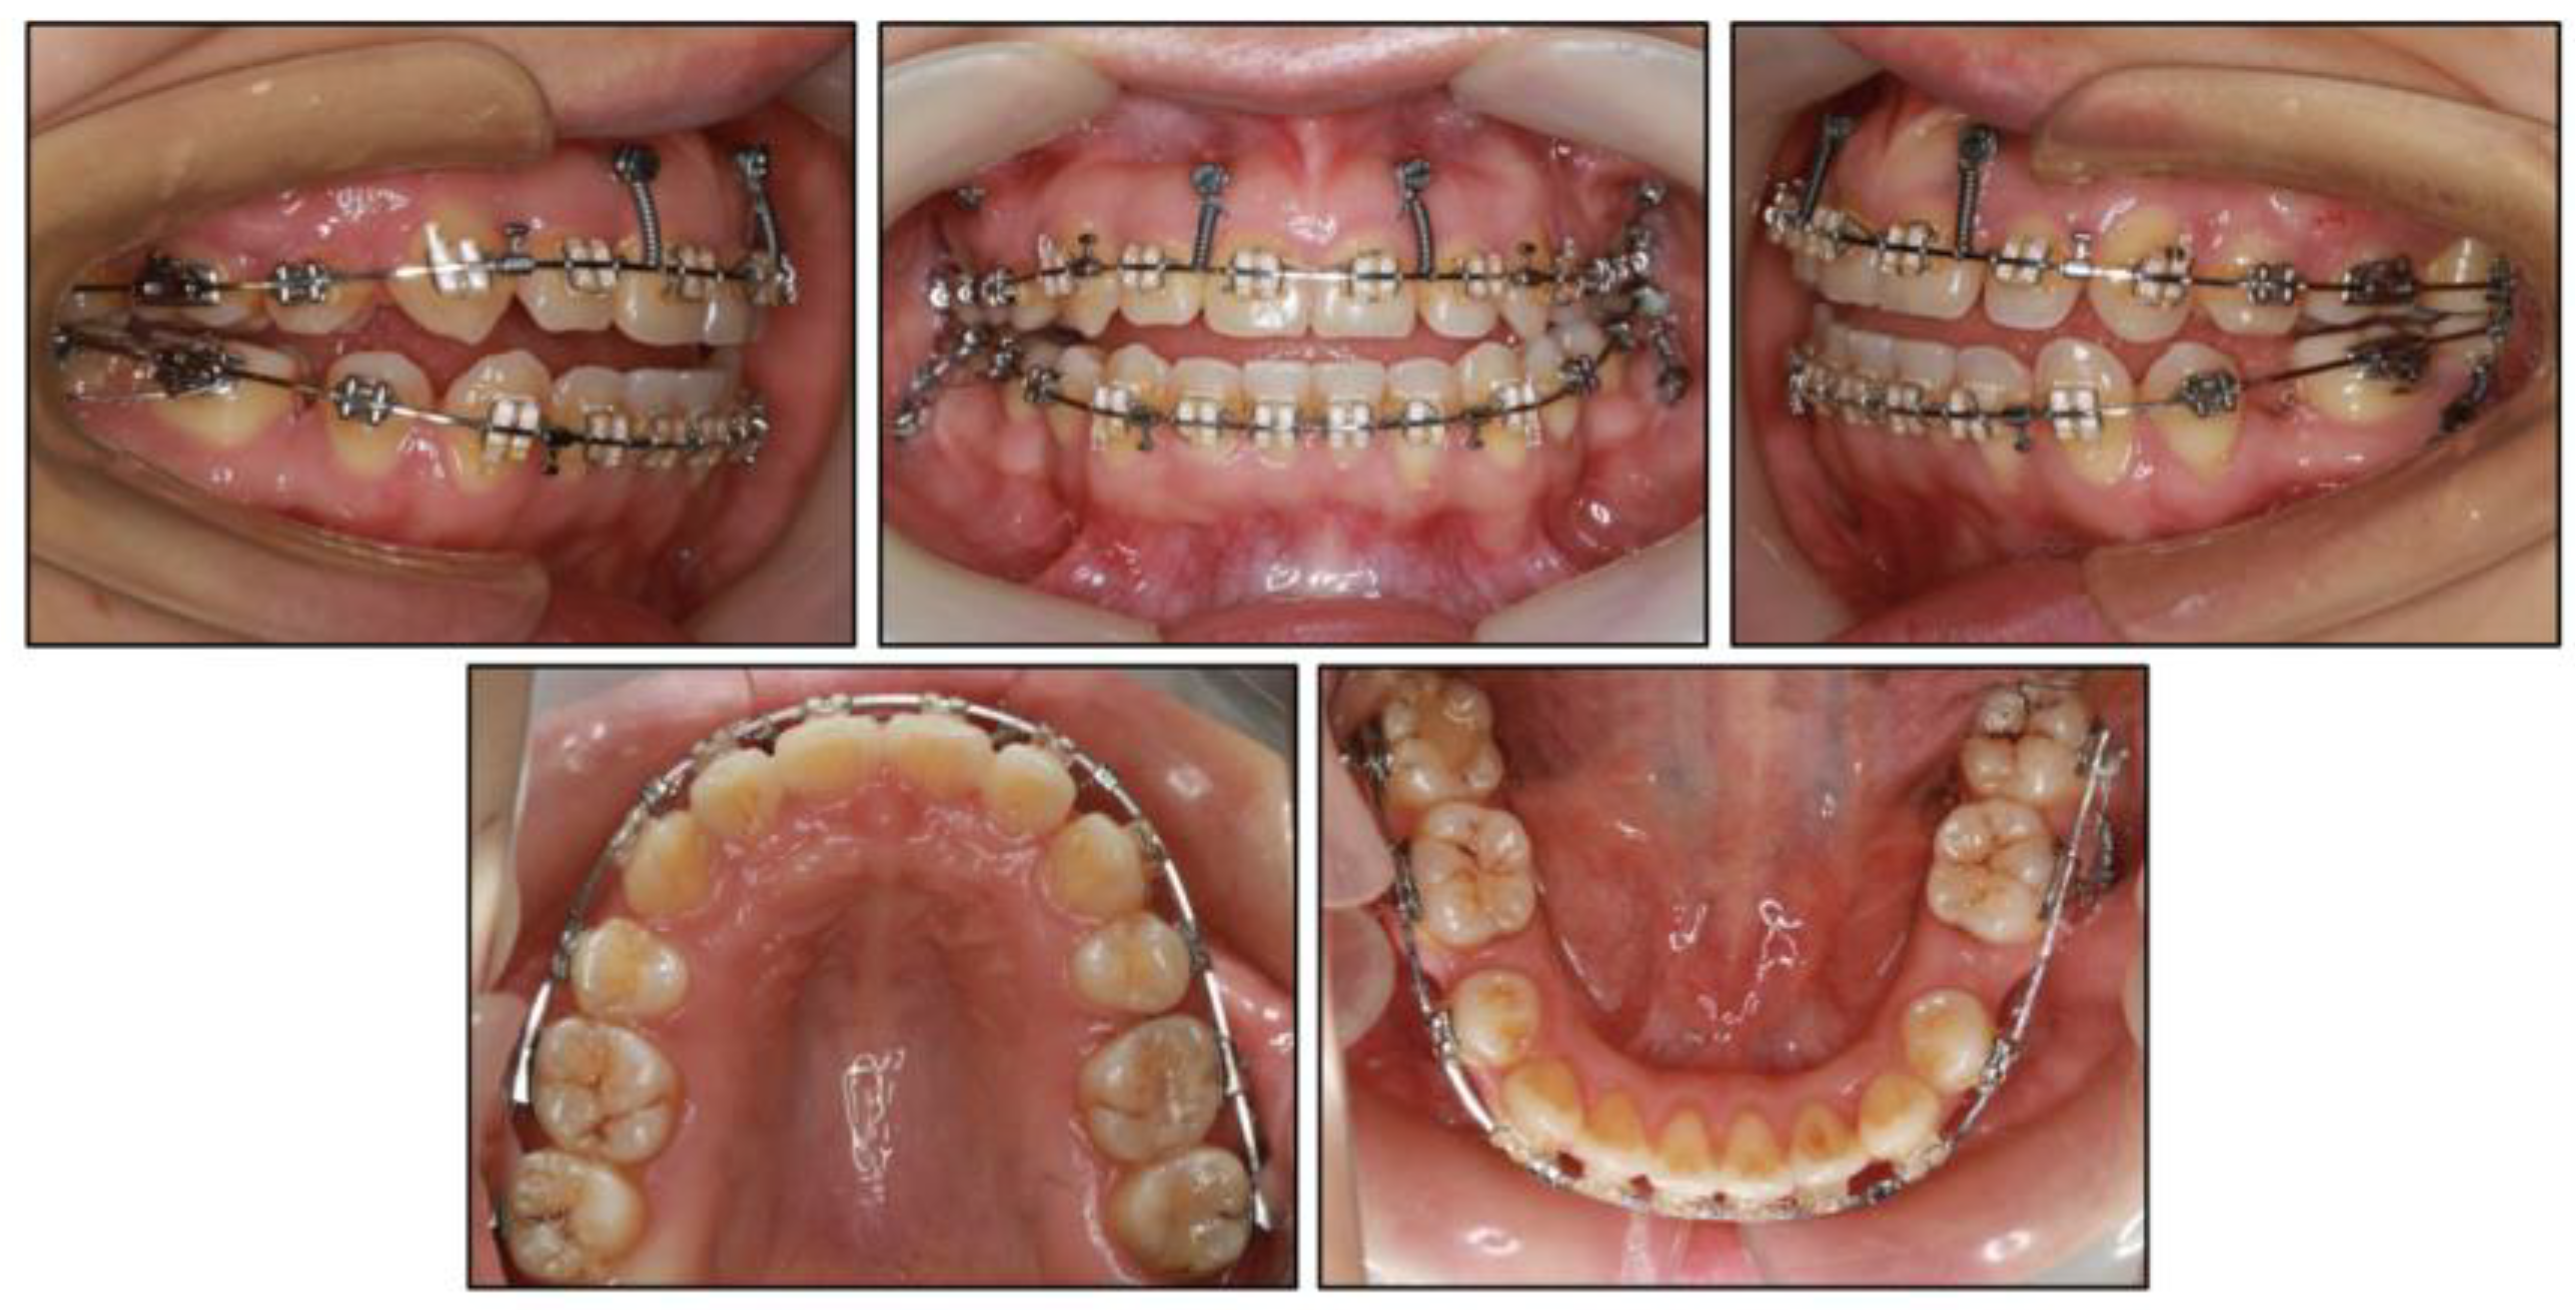

2.4. Treatment Progress